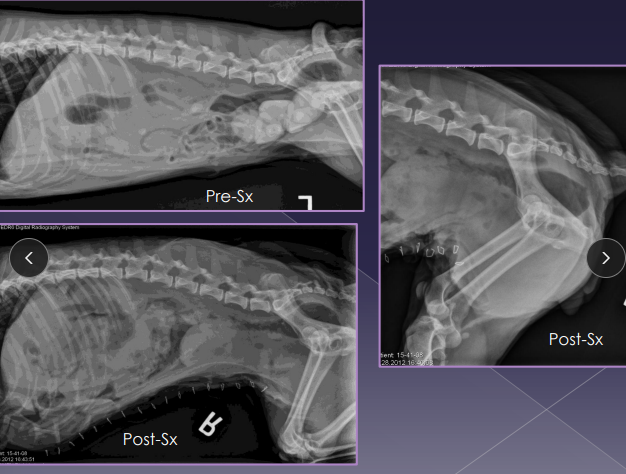

Dt: rectal exam, contrast rads, US

Tx: Sx (#1), Palliative: stool softeners, enemas, fiber

castration + herniorrhaphy: internal obturator flap, coccygeus of anal sphincter and sacrotuberous lig

stabilize bladder entrapment w/ catheterization/cystocentesis before Sx